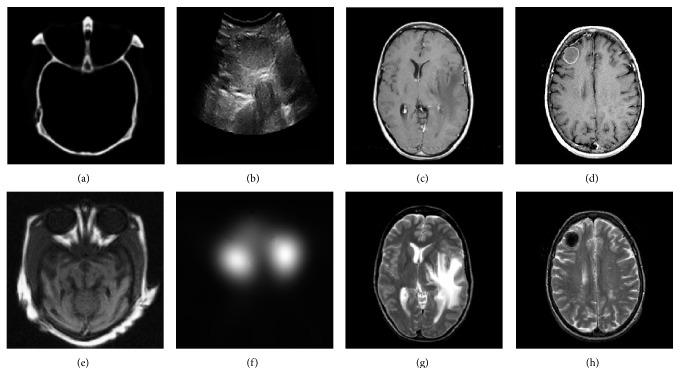

Medical image fusion plays an important role in diagnosis and treatment of diseases such as image-guided radiotherapy and surgery. Although numerous medical image fusion methods have been proposed, most of these approaches are sensitive to the noise and usually lead to fusion image distortion, and image information loss. Furthermore, they lack universality when dealing with different kinds of medical images. In this paper, we propose a new medical image fusion to overcome the aforementioned issues of the existing methods. It is achieved by combining with rolling guidance filter (RGF) and spiking cortical model (SCM). Firstly, saliency of medical images can be captured by RGF. Secondly, a self-adaptive threshold of SCM is gained by utilizing the mean and variance of the source images. Finally, fused image can be gotten by SCM motivated by RGF coefficients. Experimental results show that the proposed method is superior to other current popular ones in both subjectively visual performance and objective criteria.

医学图像融合在诸如图像引导放疗和手术等疾病的诊断和治疗中发挥着重要作用。尽管已经提出了许多医学图像融合方法,但这些方法大多对噪声敏感,通常会导致融合图像失真和图像信息丢失。此外,它们在处理不同类型的医学图像时缺乏通用性。在本文中,我们提出了一种新的医学图像融合方法来克服现有方法的上述问题。它是通过结合滚动引导滤波器(RGF)和脉冲皮层模型(SCM)实现的。首先,RGF可以捕捉医学图像的显著性。其次,利用源图像的均值和方差获得SCM的自适应阈值。最后,由RGF系数驱动的SCM可以得到融合图像。实验结果表明,该方法在主观视觉性能和客观标准方面均优于其他当前流行的方法。